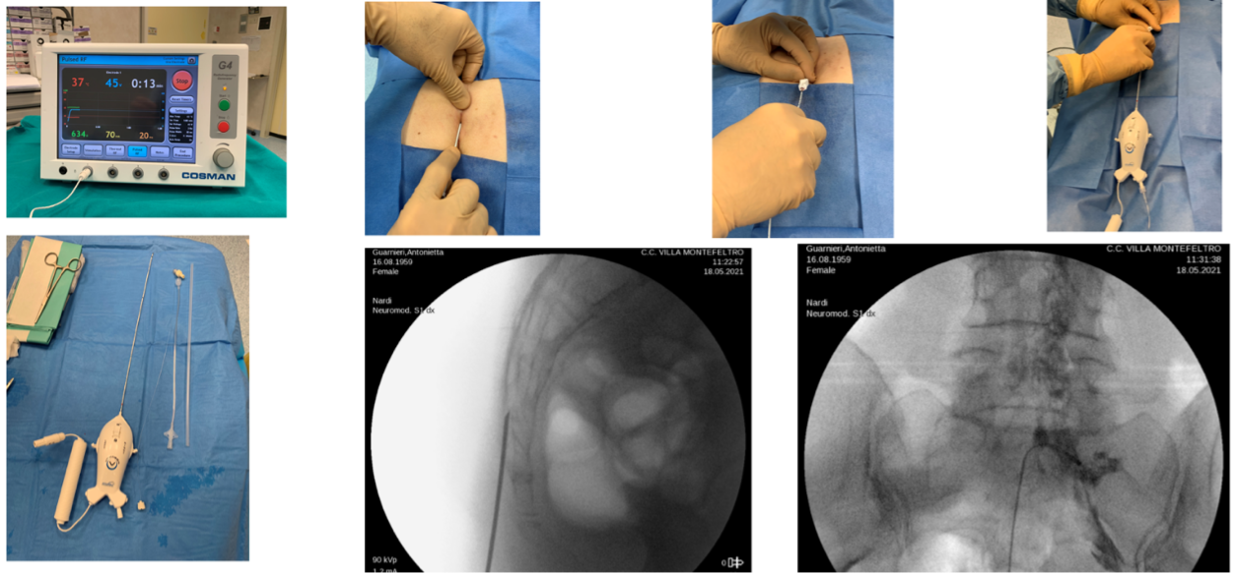

COMBINED USE OF PALMITOYLETHANOLAMIDE + EQUISETUM AND ACETYL L-CARNITINE BEFORE AND AFTER RACZ PERIDURAL ADHESIOLYSIS AND LUMBAR GANGLION NEUROMODULATION

C. Paoletti, L.F. Nardi, F. Del Sordo | Pain Relief Surgery Unit, Casa di Cura Villa Igea, Ancona